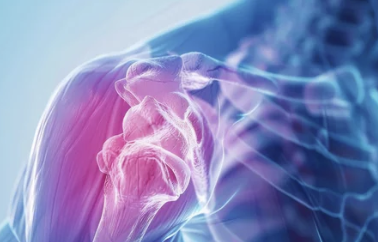

쇄골은 우리 몸에서 상체를 연결하는 중요한 뼈로, 어깨와 가슴을 이어주는 역할을 해요. 그러나 위치상 외부 충격에 취약해 쉽게 골절이 발생할 수 있어요.